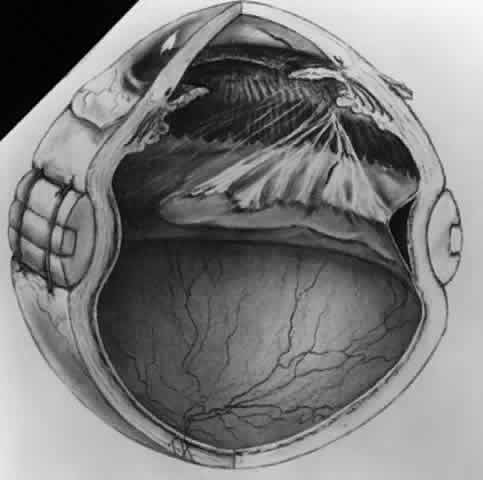

at the vitreous base and consequent rhegmatogenous retinal detachment (Fig. 7).20 Retinal incarceration in a scleral perforation produces a less common

but equally characteristic traction retinal detachment (Fig. 8). Retinal folds radiate from the site of incarceration. Associated vitreous

prolapse and entrapment cause traction on the adjacent vitreous

base with consequent detachment of the underlying peripheral retina and

pars plana epithelium. A retinal fold is created at the posterior border

of the vitreous base, which becomes increasingly prominent because

of the contracture of membranes interposed between the vitreous base

and the incarceration site. Progressive traction by this membrane may

cause breaks in the folded retina and consequent rhegmatogenous detachment (Fig. 9).  Fig. 6. Transvitreal traction causes tractional retinal detachment (A) opposite

Fig. 8. Retinal incarceration in scleral perforation. Fibrous proliferation from

wound (A). Vitreous membrane (B). Retinal folds (C). Detached pars plana

epithelium (D). Fold at posterior vitreous base border (E). (Cox MS, Freeman HM: Retinal detachment due to ocular penetration. I. Clinical

characteristics and surgical results. Arch Ophthalmol 96:1355, 1978. Copyright 1978, American Medical Association.) Fig. 8. Retinal incarceration in scleral perforation. Fibrous proliferation from

wound (A). Vitreous membrane (B). Retinal folds (C). Detached pars plana

epithelium (D). Fold at posterior vitreous base border (E). (Cox MS, Freeman HM: Retinal detachment due to ocular penetration. I. Clinical

characteristics and surgical results. Arch Ophthalmol 96:1355, 1978. Copyright 1978, American Medical Association.)